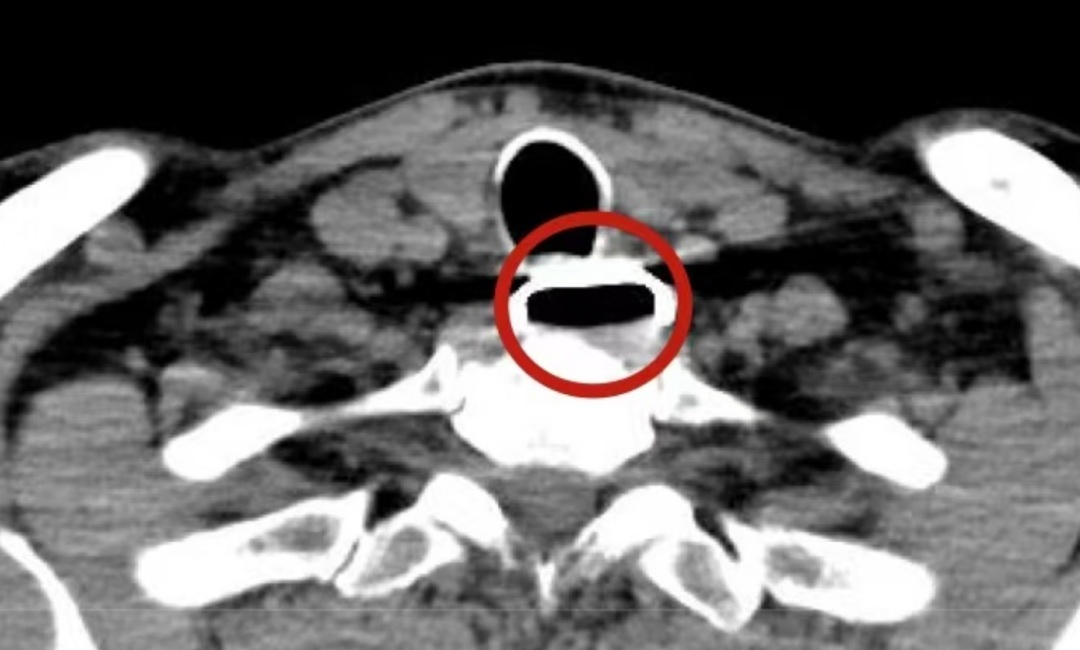

急诊团队迅速应对,颈部CT显示:直径3.2cm的高密度影正卡在食管狭窄处,紧紧压迫前方的气管……